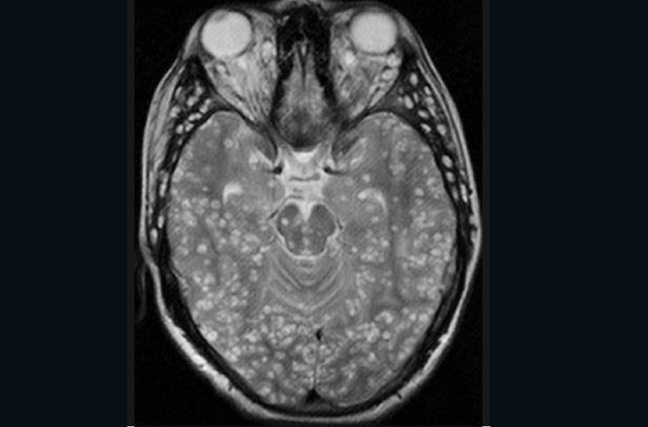

| Cận cảnh loài giun sán làm tổ trong não người |

Người bệnh này đến từ Trung Quốc và đã nhập viện vài ngày sau khi trở lại từ chyến trở về thăm quê hương mình cùng với Hàn Quốc, Nhật Bản và Thái Lan. Tại các quốc gia này, tồn tại một loại ký sinh trùng có tên khoa học là Spirometra Erinaceieuropaei.

"Khi anh ta trở lại, anh ta gặp phải những triệu chứng mới" - Bác sĩ Gkrania-Klotsas nói về bệnh nhân của mình. Có thể lý giải rằng, con giun đã di chuyển sang một vùng khác của não bộ, khiến cho việc vận động các chi của người đàn ông kém dần đi. Hội chứng này gọi là Sparganosis (bị ảnh hưởng từ ký sinh trùng).

Từ năm 1953 đến 2013, trên thế giới có khoảng 300 vũ lây nhiễm ký sinh trùng dạng Spirometra như thế này. Các bệnh nhân chủ yếu sống hoặc có đi qua châu Á - nơi được cho là vùng sinh sống của loài giun ''ăn não''.